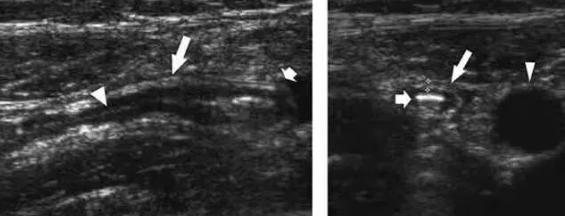

為病變早期,闌尾主要改變是充血、水腫和白細(xì)胞浸潤,炎癥局限于粘膜和粘膜下層,故超聲圖像以粘膜增厚為主,闌尾呈增粗的管狀低回聲盲端結(jié)構(gòu),表面光滑,層次尚清楚,橫斷面呈“靶環(huán)征”,闌尾周圍無或有少量積液。